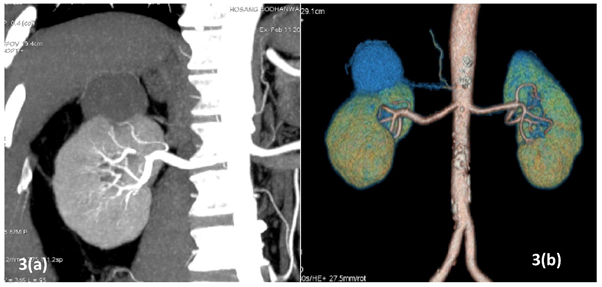

All patients underwent pre-operative contrast-enhanced computed tomography (CECT) of abdomen with renal angiography for tumour and vascular anatomy with 3D reconstruction (Figure 1). Routinely ipsilateral ureteric catheter was placed after anaesthesia. Surgical steps that were sequentially followed in all cases included ipsilateral colonic mobilization along with identification of ureter, gonadal vessels and psoas muscle; identification and mobilization of the renal artery and vein; mobilisation of the upper pole according to the need; demarcation of the tumour boundary with the help of intraoperative ultrasound; hilar clamping (renal artery and vein separately clamped); resection of the tumour; two layered renorrhaphy (Figure 2) with barbed suture with application of haemostatic agents (Gelatin granules with human thrombin and oxidised regenerated cellulose) and peri-renal drain placement. Zero-ischemia RPN were performed premeditatedly for cases with small (<4cm) cortical renal mass (predominantly exophytic) in favourable positions (lateral, lower and upper pole) and where single isolated feeder vessel was well identified (Figure 3). Ipsilateral ureteric catheter was removed routinely on 2nd post-operative day. We replaced the ureteric catheter with double-J stent where pelvicalyceal system were opened intraoperatively or tumour was larger one in vicinity to the pelvicalyceal system.

Figure 3 (a) right upper pole renal mass selected for zero ischemia (b) 3D reconstruction.